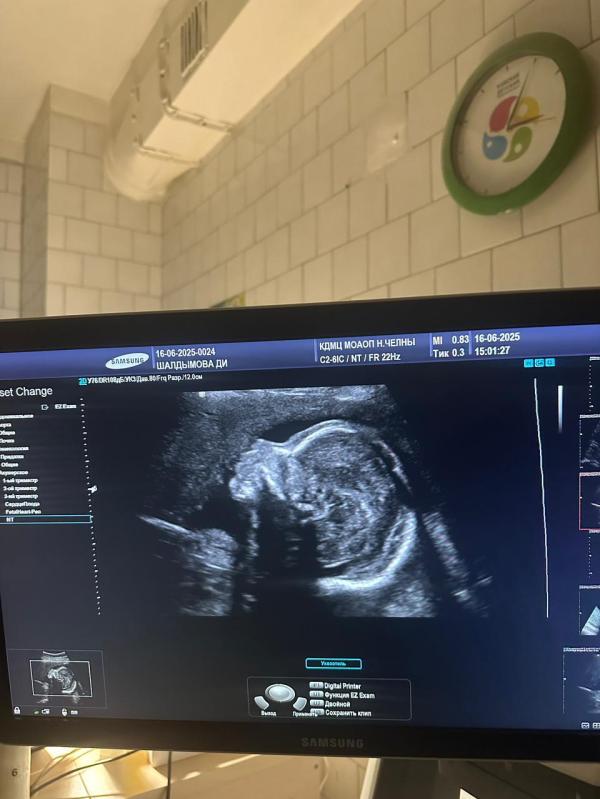

В понедельник был второй скрининг, как же я была рада увидеть наше чудо на экране монитора, кажется, что это самый красивый малыш на свете😍